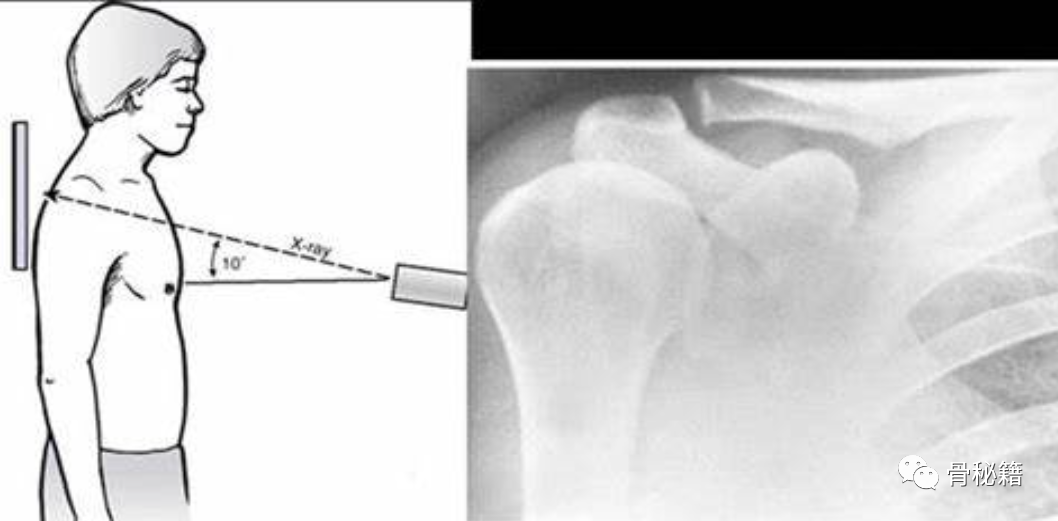

X线照片是用于评估疑似 AC 病理实体的初始且通常唯一的成像方式 。AC 关节在标准 AP 肩部 X 光片上可见,但它的角度不一且通常过度穿透。AP 成角度的 Zanca 视图更适合评估 AC 关节和锁骨远端。

光束以关节为中心,向头侧倾斜 10°–15°,从而穿过较薄的组织,优化穿透力,降低辐射剂量,并减少锁骨和肩胛骨的重叠。额外的放射投影,如腋窝和侧位片也很重要,特别是对于评估水平面不稳定性。